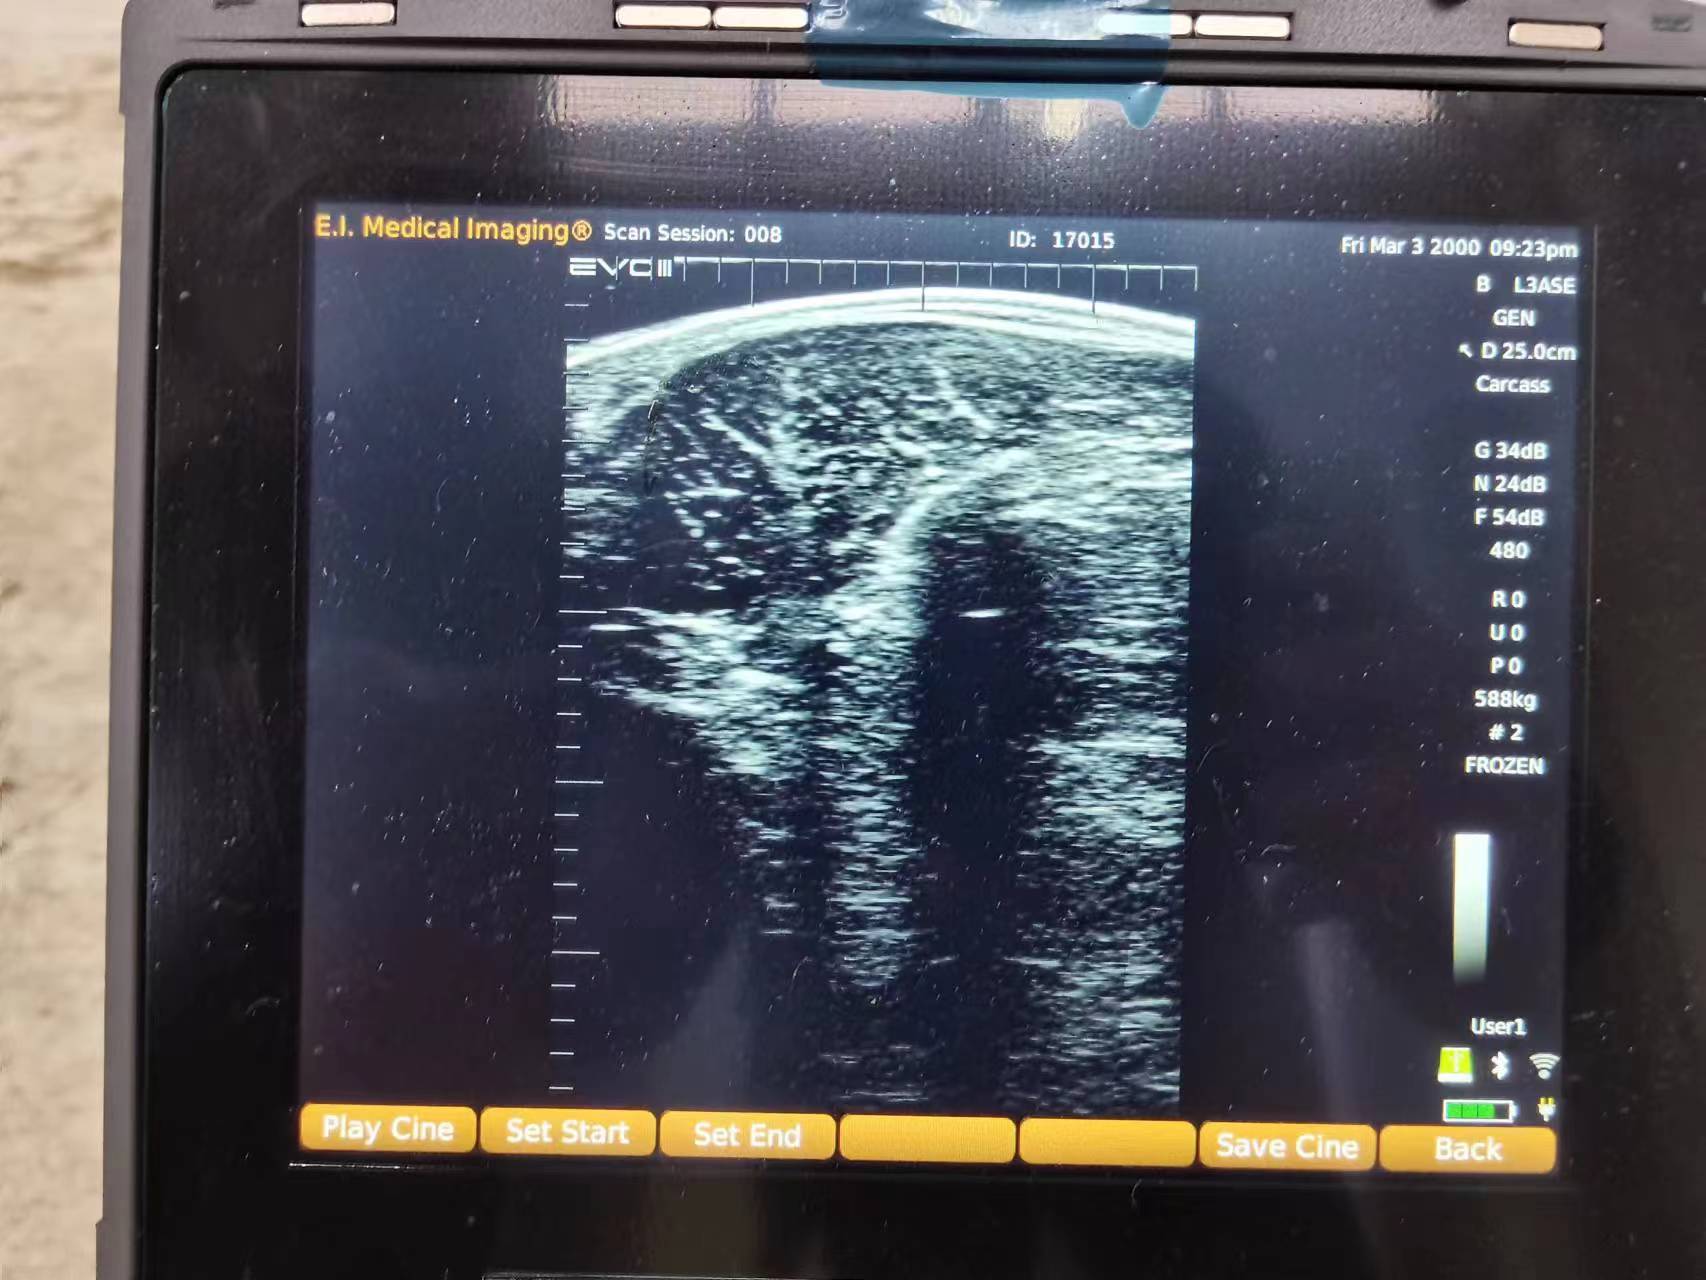

用于测量胴体特征的超声波技术被称为牛用B超及,这种技术利用高频声波(通常为2至10MHz)来显示活体动物皮下的肌肉和脂肪图像,类似于应用于牲畜和人类妊娠诊断的技术。整个过程对动物和技术人员都是安全的,无需担心任何伤害。

在检测过程中,声波探头或换能器被放置在动物背部,声波穿透组织并在皮肤、脂肪和肌肉层之间的边界处反射。当这些声波反射回探头时,超声波机器的显示器上会形成一个横截面图像,从而可以测量各种胴体特征。

肉牛眼肌面积大小超声图像